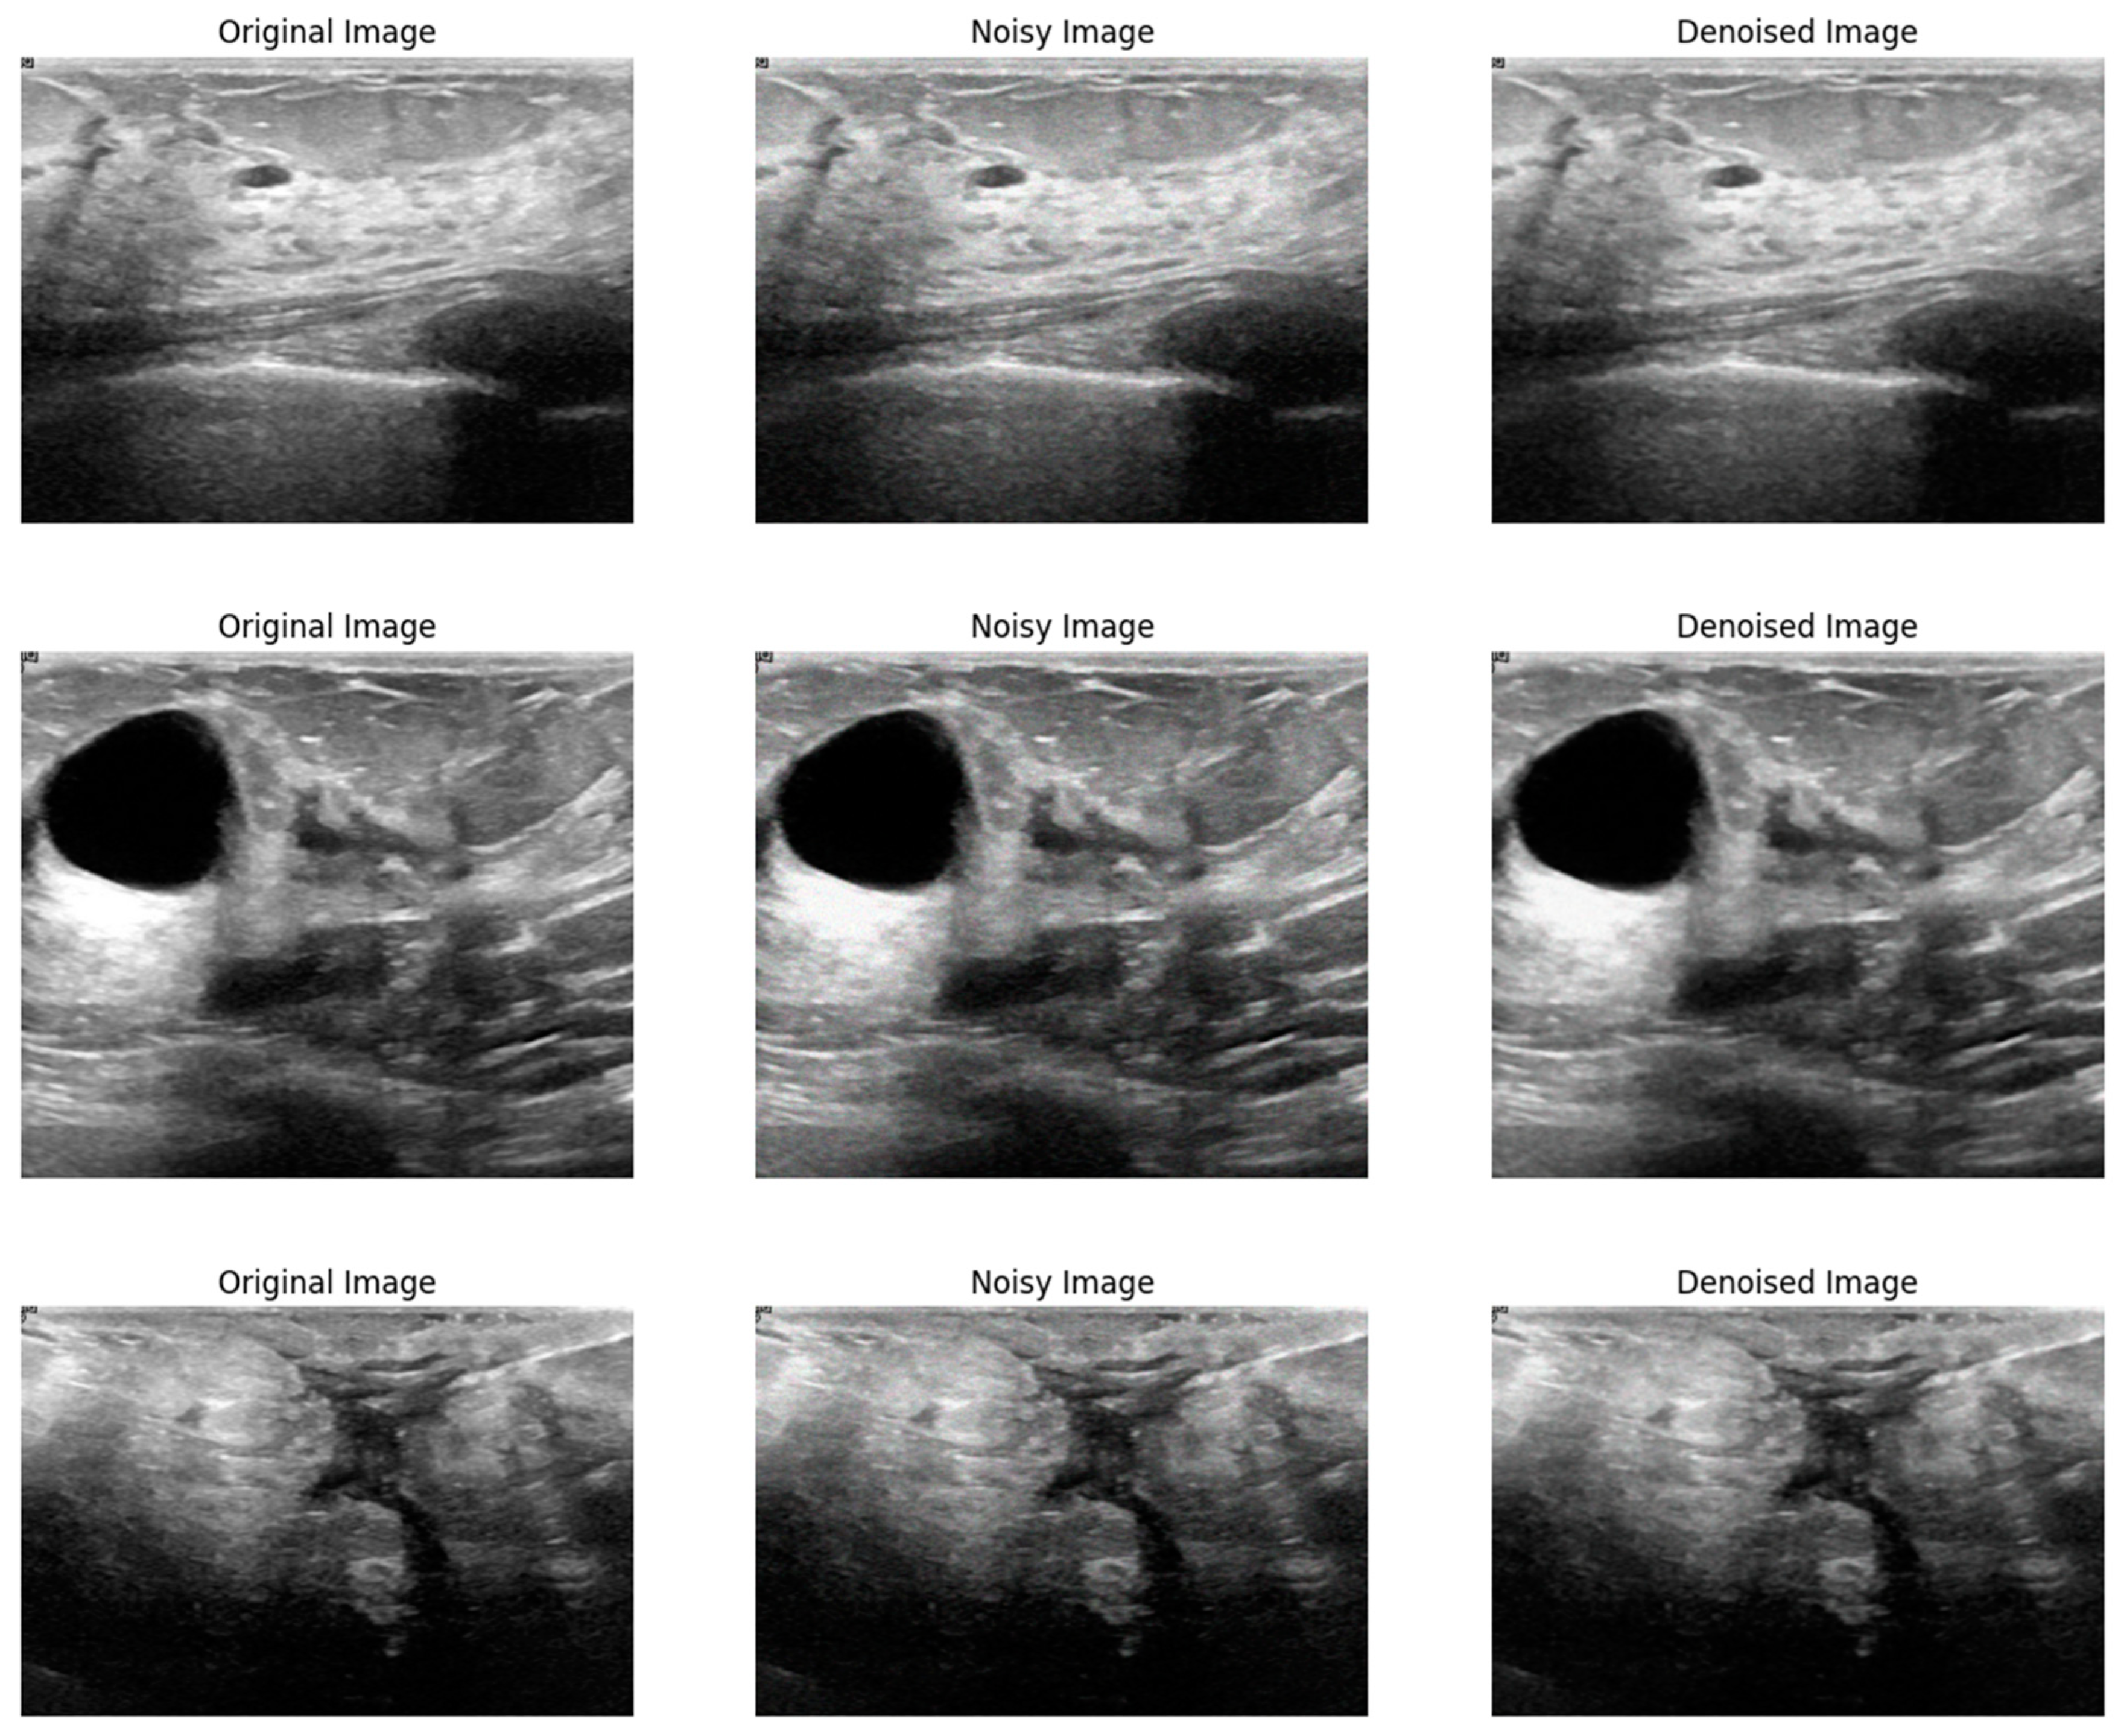

Figure 3 shows a visual comparison of the original image, the image corrupted by Poisson noise, and the denoised image produced using the proposed method. The original image serves as a baseline, displaying clear and noise-free content. The second image illustrates the significant noise introduced by Poisson distortion, which impacts image clarity and detail. In contrast, the final image demonstrates the effectiveness of the proposed denoising method, showing a substantial reduction in noise and an enhancement in image quality while preserving critical details. This comparison highlights the ability of the proposed method to effectively restore the image and mitigate the adverse effects of Poisson noise.

Figure 3.

Visual comparison of the proposed method on Poisson noise.